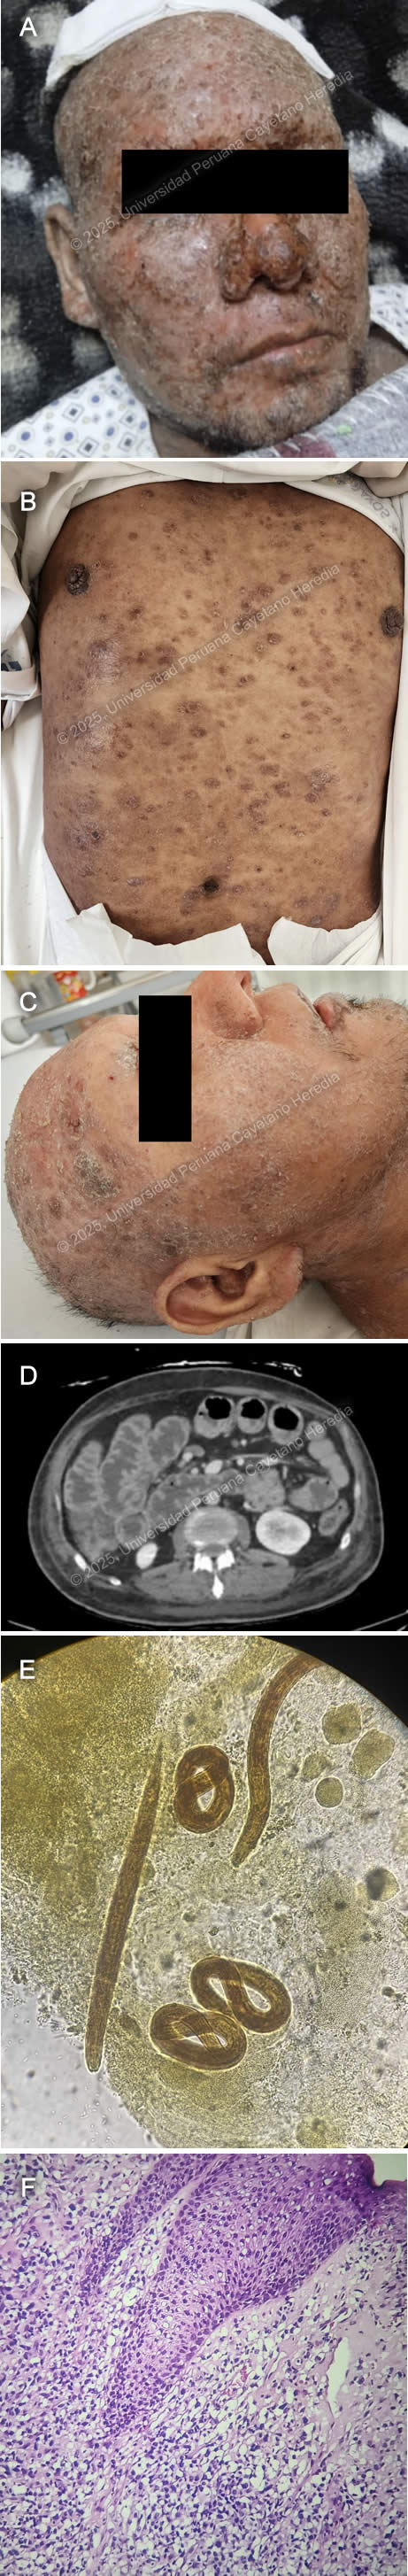

![]() History: A 68-year-old male patient with a history of benign prostatic hyperplasia presented to the emergency department with a 7-month history of scaly skin lesions spread across the body, along with severe itching. Seven months prior to admission, the patient developed itchy, scaly lesions on both lower legs. Six months before admission, similar lesions appeared on the upper extremities and chest, accompanied by worsening itching. The skin lesions gradually spread, eventually covering the entire body surface. Initially, he was presumptively diagnosed with psoriasis at another facility and was started on oral medication with no clinical improvement. The lesions on his feet and hands became painful and limited his mobility, prompting him to seek emergency care. Epidemiology: The patient was born in Ancash, a city located at 3,052 meters above sea level in the highlands of Peru, where he lived until he was 5 years old. He currently resides in Lima. He reports traveling regularly through the jungle since 1980. He works as a cleaning staff member at churches. He reports frequent alcohol consumption and use of inhaled drugs. Physical Examination on admission: BP: 130/60, RR: 17, HR: 94, Sp02 98% on room air, T 37.6°C. The patient was not in acute distress. Thick, whitish, crusted plaques with an erythematous base, some exhibiting surface fissures and erosions, were seen on the arms, anterior chest wall, and abdomen. The palmar surfaces revealed several scaly papules and plaques involving the palmar creases. Fingernails exhibit nail dystrophy, onychorrhexis, and thickening of the nail plates. All toenails demonstrated nail plate thickening, onychodystrophy, and xanthonychia. (Images A,B,C,D). The rest of the exam was non-contributory. Laboratory: Hemoglobin 12.8g/dL; hematocrit 37%; WBC 36000/µL with bands 0%, neutrophils 70%, eosinophils 14% (absolute 1900/µL), basophils 0%, monocytes 7% and lymphocytes 9%. Platelets 406000/µL. Creatinine 0.95 mg/dL; urea 33 mg/dL; AST 24 IU/l; GGT 18 IU/L. INR was 1.14. Glucose 112 mg/dL; sodium 137 mEq/l; potassium 3.86 mEq/l, and chloride 102 mEq/l. Serology for HIV, hepatitis C, and hepatitis B were negative. The HTLV-1 chemiluminescent immunoassay was positive. Chest X Ray was non-contributory. Skin scrape microscopy is shown in Images E,F. UPCH Case Editors: Carlos Seas, Course Director / Paola Nakazaki, Associate Coordinator |

Discussion: The skin scrape microscopy shows structures typical of Sarcoptes scabiei. The Human T-cell Lymphotropic Virus type 1 is a retrovirus of the Retroviridae family. First identified in the early 1980s, it is known to exhibit a strong tropism for CD4+ T lymphocytes and establishes a persistent, lifelong infection in the host (1). Transmission occurs primarily through vertical routes such as breastfeeding, as well as through horizontal mechanisms including sexual contact, blood transfusion, and intravenous drug use (1,2). HTLV-1 infection is a neglected tropical disease with an estimated prevalence of 5 to 10 million carriers globally. It is endemic in certain regions, including southwestern Japan, the Caribbean, parts of South America, sub-Saharan Africa, and areas of the Middle East and Australia. Despite its clinical significance, HTLV-1 remains under limited public health surveillance and lacks effective antiviral therapies or vaccines (1,3). Although many infected individuals remain asymptomatic, the virus can cause severe diseases such as adult T-cell leukemia/lymphoma (ATLL) and HTLV-1-associated myelopathy/tropical spastic paraparesis (HAM/TSP). HTLV-1 infection induces a chronic state of immune dysregulation, predominantly affecting cell-mediated immunity via alterations in CD4⁺ T-cell subset polarization, impaired cytotoxic T lymphocyte responses, and dysregulated cytokine networks. These immunologic perturbations predispose individuals to a distinct spectrum of infectious diseases, many of which exhibit increased severity, chronicity, or dissemination in the context of HTLV-1 seropositivity (1). The most well-established and clinically significant association is with Strongyloides stercoralis with a marked increased risk of developing the hyperinfection syndrome (see Case of the Week 03-2012), characterized by uncontrolled proliferation and dissemination of larvae, often leading to severe gastrointestinal, pulmonary, and systemic complications (4, 5). An increasingly recognized clinical association exists between Sarcoptes scabiei var. hominis hyperinfestation, commonly referred to as crusted scabies, and HTLV-1 infection, as its immune dysregulation contributes to both susceptibility and severity of infestation (6). The extreme mite proliferation, reaching millions per host, renders the condition highly contagious, with transmission possible via minimal direct contact or fomite exposure. It is characterized by extensive hyperkeratotic skin lesions, often with overlying crusts and fissures that can be distributed across the scalp, face, trunk, extremities, and periungual regions. Nail dystrophy and subungual hyperkeratosis are frequently observed, and in severe cases, the infestation may extend to mucocutaneous junctions. It can be accompanied by pruritus; however, it can be absent or attenuated due to blunted inflammatory responses in individuals with impaired cell-mediated immunity. Crusted scabies presentation can also mimic other dermatologic conditions such as psoriasis, eczema, or keratoderma, complicating clinical diagnosis (7). During hospitalization, our patient presented with fever, and developed Staphylococcus aureus (MSSA) bacteriemia. Secondary bacterial colonization, often with Staphylococcus aureus or Streptococcus pyogenes, is a common case of crusted scabies and can precipitate systemic sequelae, including bacteremia and sepsis (7). Currently, there is no curative or antiviral therapy available that can eliminate HTLV-1 infection. Management is therefore focused on treating HTLV-1–associated diseases and providing supportive care. Treatment approaches vary significantly depending on the clinical manifestation, most notably adult T-cell leukemia/lymphoma (ATLL), depending on the clinical subtype, and HTLV-1–associated myelopathy/tropical spastic paraparesis (HAM/TSP), with limited evidence (8, 9). Prophylactic antiparasitic therapy with ivermectin is recommended in endemic areas to prevent Strongyloides hyperinfection (5). Public health strategies focus on preventing transmission, including blood donor screening, avoidance of breastfeeding by infected mothers, and safe sexual practices (1). Monitoring the proviral load, neurological progression, and oncogenic transformation is essential in long-term management. Treatment should be combined with environmental decontamination and isolation precautions to prevent the transmission of the disease. Our patient was started on ivermectin for 3 days and repeated the dose for three more days. One week later, permethrin 5% was applied to the lesions all over the body daily. MSSA bacteremia is being managed with oxacillin. References |